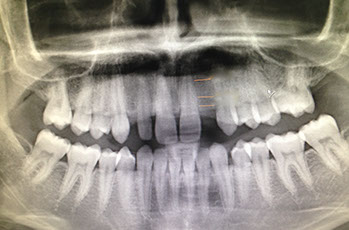

riabilitazione completa su impianti

due casi all on four carico immediato

agenesia di un incisivo laterale